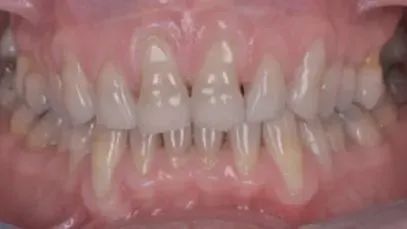

牙龈萎缩的常见原因主要包括以下几方面:

✎ 牙周炎:这是较为常见的原因,牙菌斑、牙结石等刺激导致牙周组织炎症,进而造成牙龈退缩。

✎ 刷牙不当:长期使用过硬的牙刷、采用横刷法等可能损伤牙龈,引起牙龈萎缩。

✎ 年龄增长:随着年龄的增加,牙龈可能会逐渐出现生理性退缩。